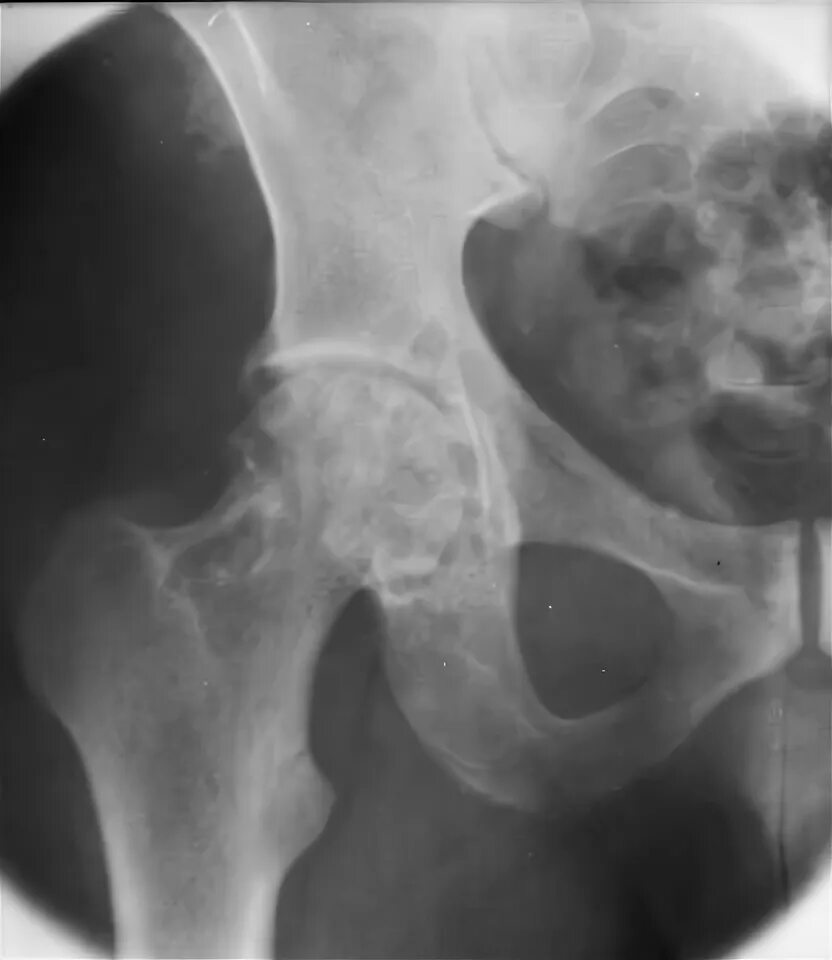

Пигментный виллонодулярный синовит